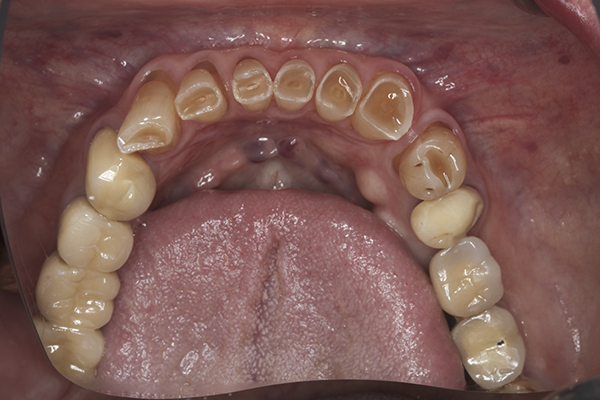

(41.) Postoperative maxillary occlusal view. Note the composite tops on teeth Nos. 12 through 14.

Figure 41